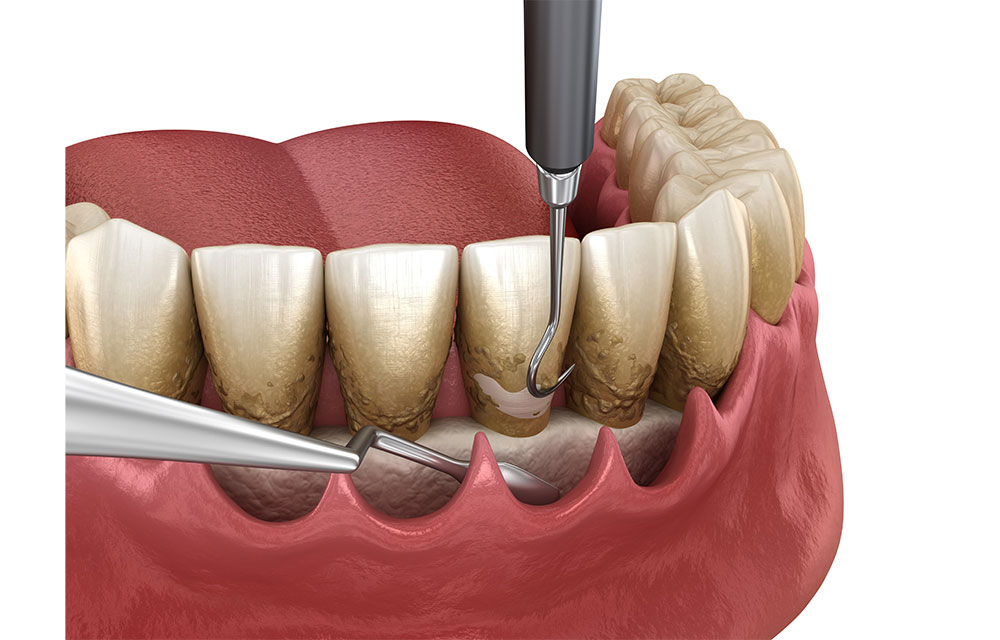

スケーリング・ルートプレーニング

ブラッシングだけで除去できないプラークや歯石は、歯医者で専用器具を使用して取り除きます。これをスケーリングと言います。また、歯石や細菌の毒素で汚染された物資を除去するルートプレーニングも同時に行います。

歯周ポケット掻爬術

歯周ポケットの内側に付着した歯石と病巣を掻き出し、歯の根と歯ぐきを密着させて縫合する治療法です。